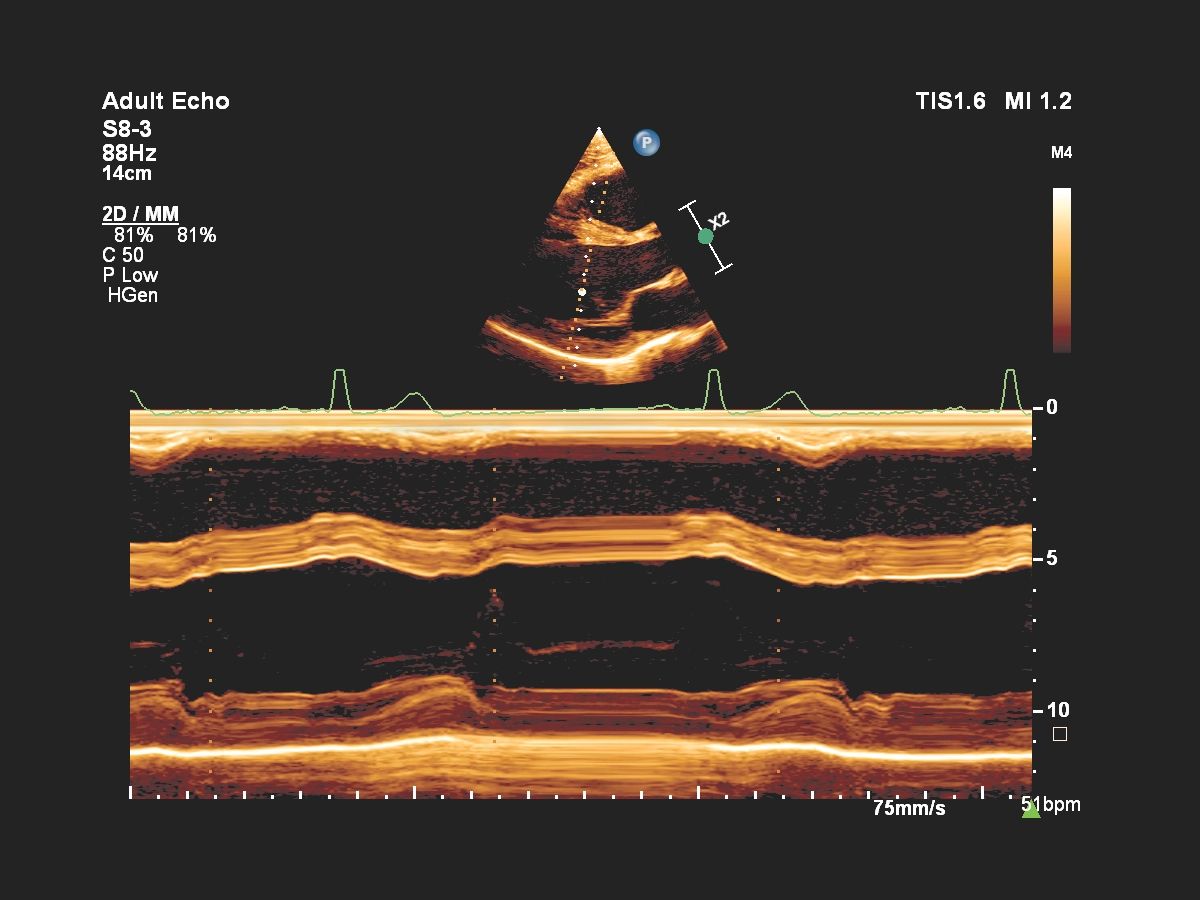

- Кардиология

Функции для кардио-исследований

- Stress Protokol - стресс эхокардиография

- GI 3DQ - количественный анализ 3D

- TDI - тканевый допплер

- Strain Q - функция для оценки скорости движения стенок миокарда

- A2DQ - автоматическое распознавание границ камер сердца и расчет площади, объема левого желудочка и параметров систолы и диастолы левого желудочка, расчет фракционной площади, фракции выброса, максимальной скорости выброса, максимальной скорости быстрого наполнения и фракции предсердного наполнения

- aCMQ - Анализ параметров общей и конкретной сократимости камер сердца

- CMQ Stress - стресс эхокардиография для оценки глобальной и регионарной сердечной функции в различных состояниях